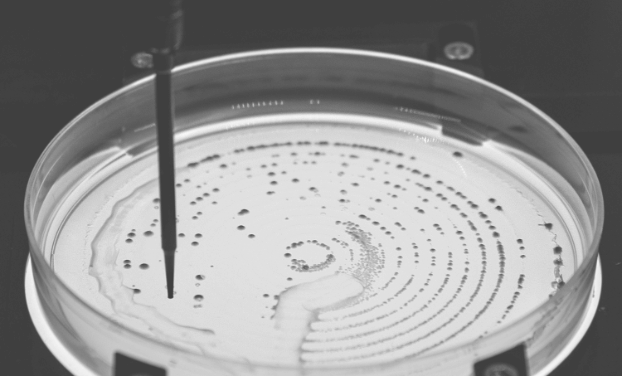

Research in Brian Cunningham’sprofessor of electrical and computer engineering (CGD leader) group also takes advantage of human-computer partnerships to evaluate data, using AI to help improve the detection of biomarkers—molecules that can indicate what is happening in the body, as well as the presence of disease. Their microscopy-based diagnostic technique generates red images with tiny black spots scattered throughout, each representing a single biomarker molecule tagged with a gold nanoparticle for visualization. Integration of a deep-learning algorithm helps to automate the counting of these spots, improving the accuracy and lowering detection limits of their method.

While the automation helps remove the need for expert analysis, the AI’s performance is tied with the quality of its training data. A speck of dust can be difficult to differentiate from a true biomarker spot, even to the trained eye. To ensure accurate counting, graduate student Han Lee spent hours cross referencing black spots against ground truth electron microscope images.

“I think that the limitation is that AI can't, by itself, actually detect the molecules. We still need the physics principles, the nanofabrication, the optics, electromagnetics, and biochemistry parts to all work together to selectively capture the biomarker and provide a signal that is above the background noise. What the AI helps with is the ability to tolerate a greater degree of background noise, so we can use less costly optical components to build a small and inexpensive instrument.”

—Brian Cunningham (CGD leader)

professor of electrical and computer engineering